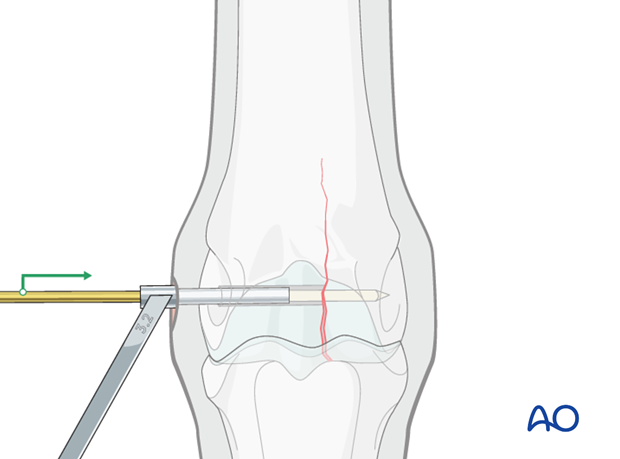

The 3.2 mm drill bit is inserted into the corresponding drill guide and the thread hole is prepared across the remainder of the bone. The drill bit should be removed and cleaned frequently because this is very dense bone.

Caution should be used when approaching the far cortex to minimize damage and debris as the drill bit exits the bone.

The 3.2 mm bit is removed and the 2.5 mm pin re-inserted. This pin is valuable to minimize any difficulties finding the hole through the stab incision.